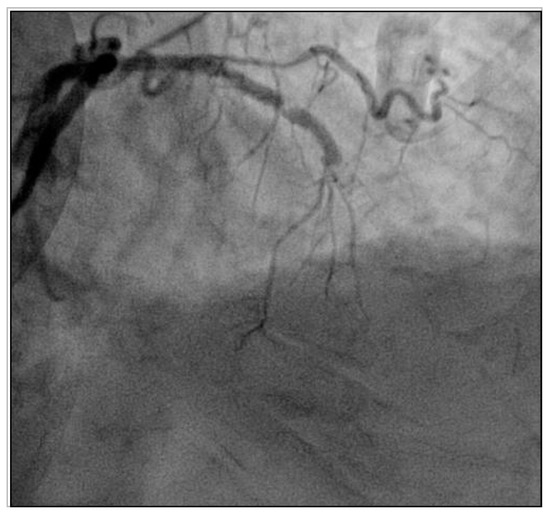

2. Case Vignette